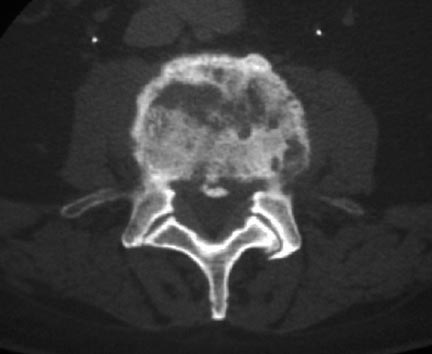

La osteomielitis vertebral, denominada a veces infección de espacio discal, discitis séptica, espondilodiscitis u osteomielitis espinal, es la manifestación más frecuente de infección hematógena de huesos en los adultos.

Se trata de un proceso patogénico que origina la afectación de vértebras vecinas y el disco intervertebral correspondiente; en adultos, dicho

disco es avascular. Los microorganismos invaden a través de arterias segmentarias las láminas terminales vecinas y después se propagan al disco.